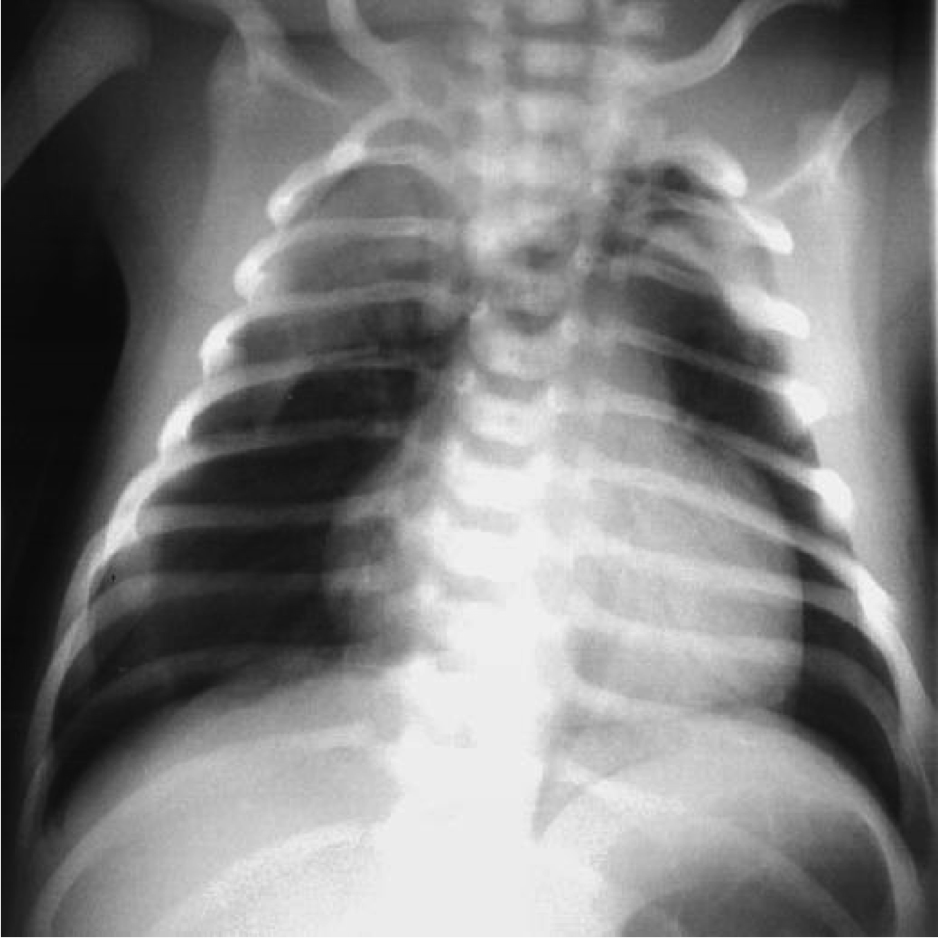

Scaphoid Abdomen In Children / Your child's health and safety are our highest priority.